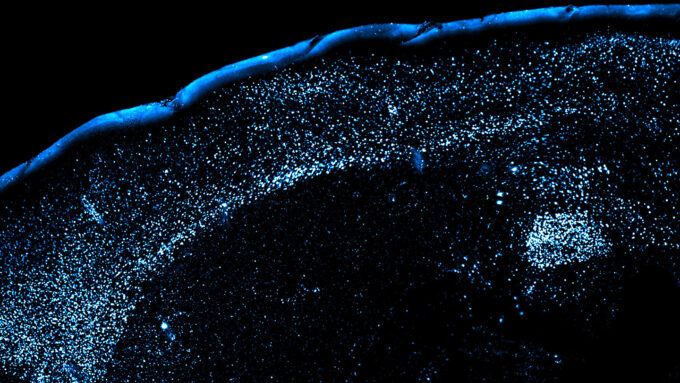

1. Brain

Mice show us why food poisoning is so hard to forget

Working with mice, scientists have mapped a brain pathway that links an unfamiliar flavor with later food poisoning symptoms.